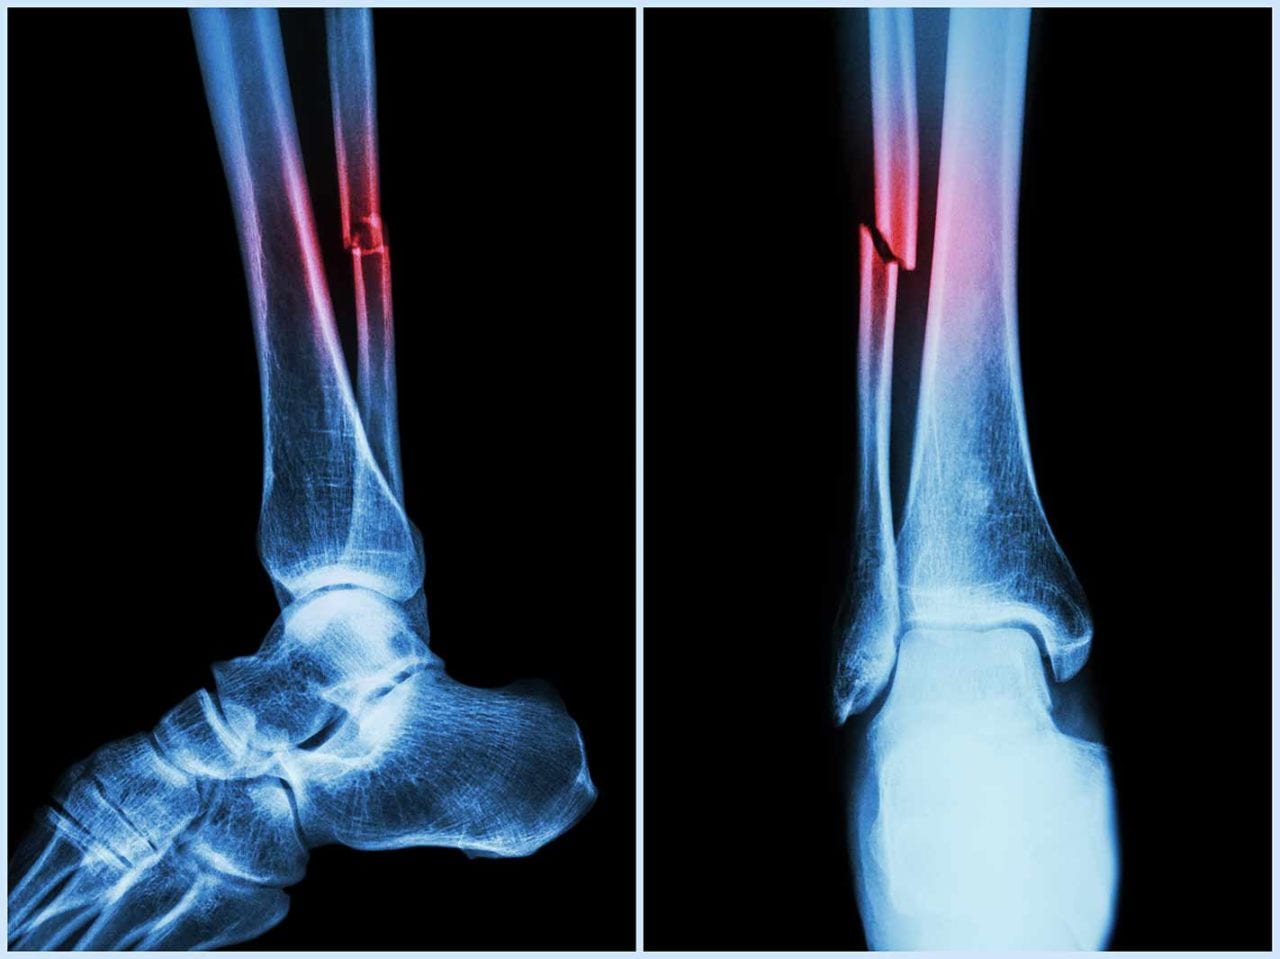

In the study, mice who had Covid-19 showed significant bone loss. This loss decreased the bone mechanical strength and increased the risk of fractures.

If similar bone loss occurs in human patients following their Covid‐19 recovery, it could leave them with a long‐term — even permanent — increased risk of fractures due to fragile bones. This is especially true in elderly patients.

The study suggested that the higher risk of fragility fractures, when a person falls from standing height or less, may be one of the underreported long-haul symptoms of Covid.

“This study has profound clinical implications,” said R. Lor Randall, professor and chair of the Department of Orthopaedic Surgery. “Musculoskeletal ramifications of Covid may not be the first medical issue that comes to mind when one thinks about the pandemic. Nevertheless, many people suffer from fragile bones and Covid can put them at an even greater risk for fracture.”